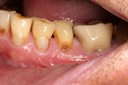

Wes Sato #14 caries removal